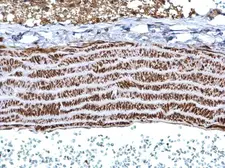

Images